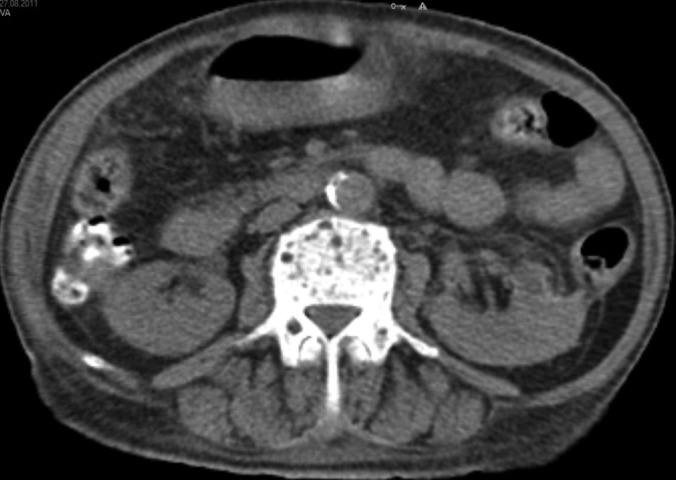

Seventeen patients underwent laparoscopic decortication of hilar renal cysts with the LigaSure system. Our study included only symptomatic, Bosniak type 1, simple and symptomatic renal cysts. The operative route, transperitoneal or retroperitoneal, was planned according to the location confirmed by computed tomography. The patients' symptoms were preoperatively and postoperatively evaluated by the Wong-Baker visual pain scale. Operative measures and radiologic outcomes were prospectively evaluated.

The mean age of the patients was 56.4 years, and the mean follow-up period was 12.5 months. Preoperative computed tomography showed only a single cyst in 15 patients (88.2%) and showed two separate cysts in 2 cases (11.8%). The cysts were located in the perihilar region close to the vascular structure in all patients. A transperitoneal approach was used in 9 patients, and a retroperitoneal approach was used in 8 patients. The mean operative time and hospitalization time were 56.4 minutes and 1.2 days, respectively. Minor complications were observed in 3 patients. Symptomatic and radiologic success rates of 94.2% and 100%, respectively, were achieved.

17例患者使用LigaSure系统接受了腹腔镜下肾门部肾囊肿去皮质术。我们的研究仅纳入有症状的Bosniak 1型单纯性有症状肾囊肿。根据计算机断层扫描确定的位置规划手术路径,经腹腔或腹膜后途径。术前和术后通过Wong-Baker视觉疼痛量表评估患者症状。前瞻性评估手术措施和影像学结果。

患者的平均年龄为56.4岁,平均随访期为12.5个月。术前计算机断层扫描显示,15例患者(88.2%)仅有单个囊肿,2例患者(11.8%)有两个独立囊肿。所有患者的囊肿均位于靠近血管结构的肾门周围区域。9例患者采用经腹腔途径,8例患者采用腹膜后途径。平均手术时间和住院时间分别为56.4分钟和1.2天。3例患者出现轻微并发症。症状缓解率和影像学成功率分别达到94.2%和100%。